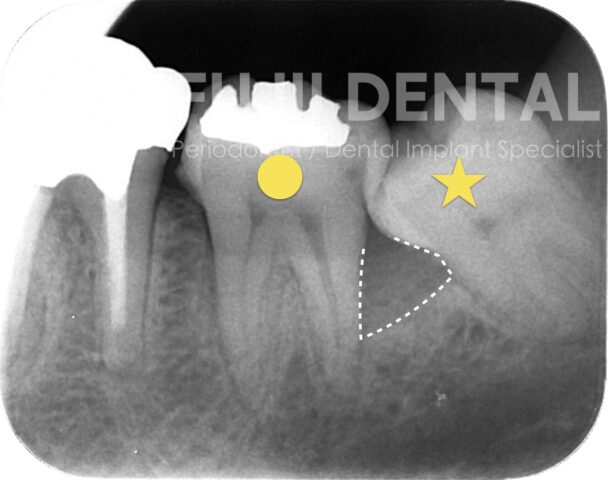

レントゲン画像では「★ 親知らず (第三大臼歯)」のために食べ物のカスや、細菌の塊であるプラークのために炎症が起き、隣り合った「● 第二大臼歯」の骨も溶けてしまっています。

「★ 親知らず (第三大臼歯)」を抜いて1年後ですが、「● 第二大臼歯」の奥の骨が溶け、深い歯周ポケットが残ってしまいました。継続的に骨が溶けていき抜歯になることが予想されます。治療の選択肢として、外科的な歯周病治療でかろうじて救えるかもしれない、ただし最悪、抜歯からインプラントを薦めなければならないこともあります。